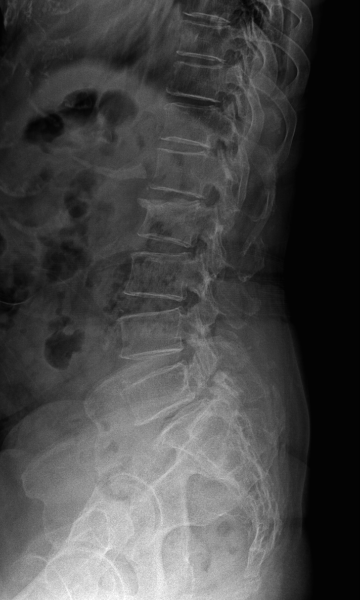

다리 저림이 심하고 보행이 힘든 경우 수술적 치료가 필요하며 척추고정술을 통해 신경 압박을 풀어줍니다.

척추전방전위증 수술 전·후

2022.09.21

2022.12.30

ㆍ환자 동의를 받은 자료이며, 이미지 사진은 실물과 다를 수 있습니다.